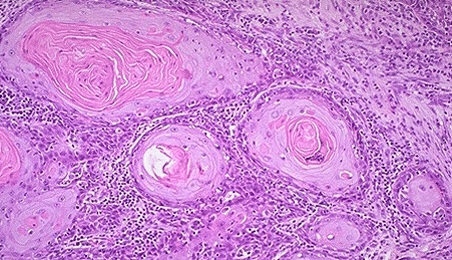

- Плоскоклеточный рак ин ситу. Данную конфигурацию обнаруживают во влагалищной доле шейки. Берет свое начало из многослойного плоского эпителия. При этой форме наблюдается ороговение некоторых клеток либо целой группы клеток. Свободно от формы, наблюдается атипия клеток, большая численность патологических митозов.

Морфологическая характеристика рака in situ

Морфология представляет собой науку, занимающуюся изучением формы, вида, цвета и структуры различных организмов или новообразований. Как же происходит морфологическая характеристика ин ситу шейки матки?

На первом этапе наблюдаются изменения в клетках эпителиального слоя. Эти клетки располагаются неправильно, имеют деформированную структуру и стремятся занять место здоровых клеток. Они теряют способность к митозу, а также претерпевают изменения в ядре, особенно в его форме и размере. Измененный эпителий проникает в железистый слой, но на стадии in situ он не проникает в базальную мембрану.